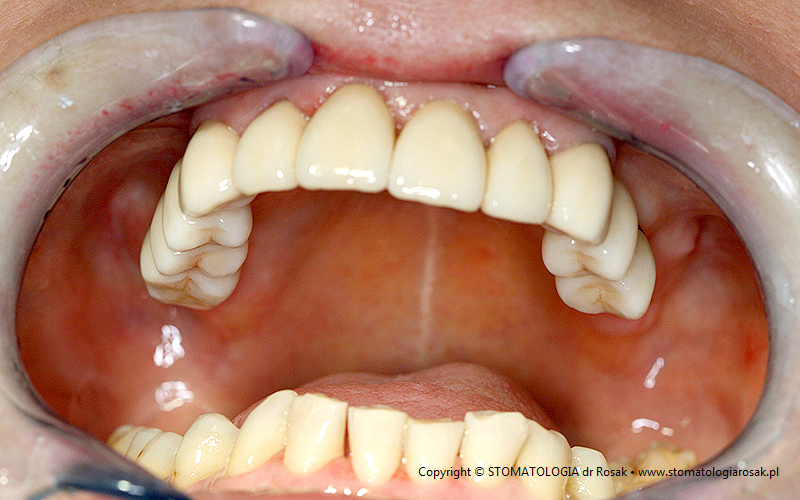

8. Pacjentka lat 61 – okrężny most porcelanowy.

| 8a. Przed leczeniem |

8b. Gotowy most |

| 8c. Gotowa praca w ustach pacjentki |

|